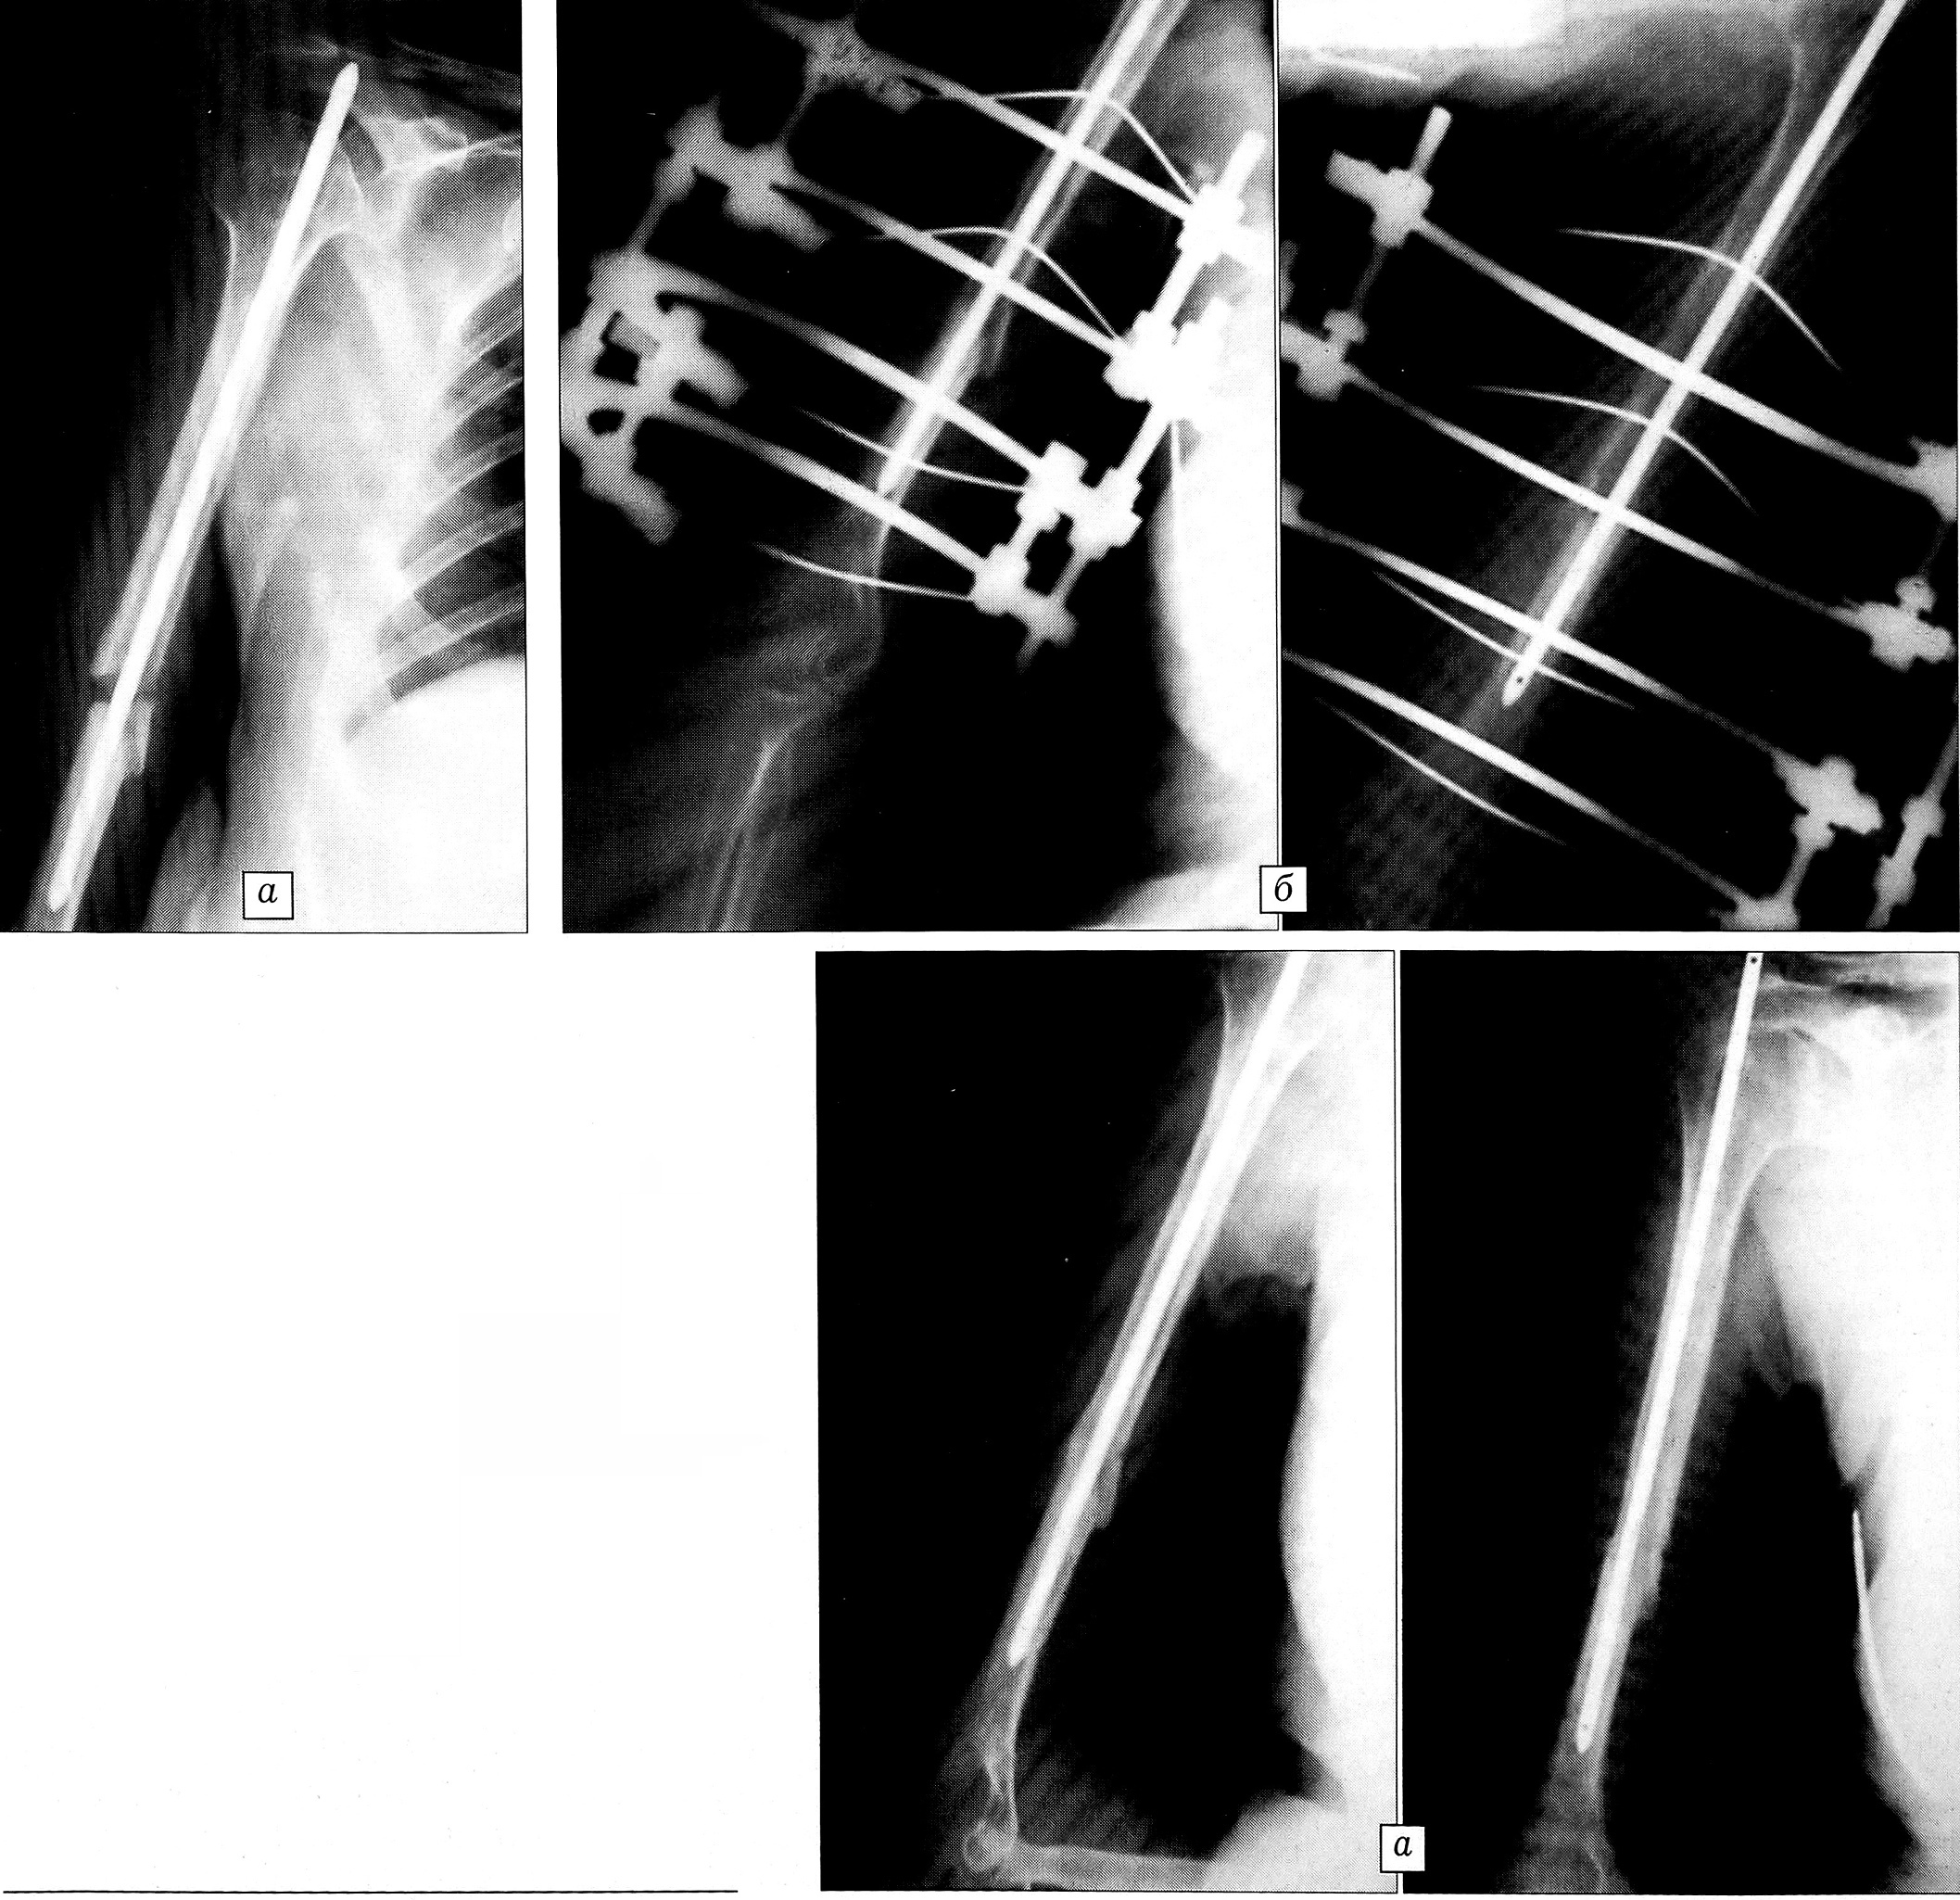

Рис. 4. Пример 4.Рентгенограммы больной Б.a — несросшийся перелом плечевой кости через 5 мес после остеосинтеза штифтом;б — после наложения аппарата наружной фиксации;в — спустя 4 мес: перелом сросся, аппарат снят.

Пример 4. Больная Б., 42 лет. По поводу закрытого перелома правой плечевой кости в одной из московских больниц через 7 дней после травмы произведен остеосинтез металлическим штифтом. Сращения перелома не наступило (рис. 4, а). Через 5 мес в ЦИТО на плечевую кость наложен аппарат из четырех скоб со спицами, произведена фиксация отломков с взаимным давлением. Через 20 дней после наложения аппарата рентгенологически определяется рассасывание рубцовых тканей между отломками, обусловленное их компрессией, сближение отломков до контакта (рис. 4, б). Через 4 мес наступило сращение перелома, аппарат удален (рис. 4, в).